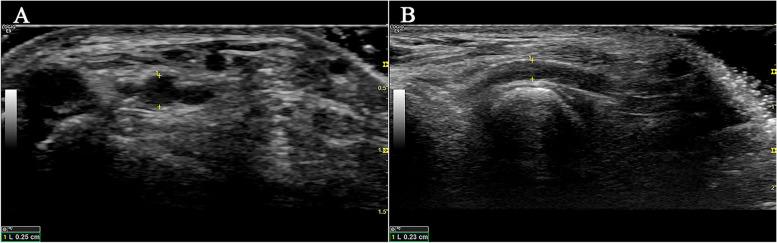

Distal radial artery approach is safe and effective for cerebral angiography and neuroendovascular treatment: A single-center experience with ultrasonographic measurement.经桡动脉远端入路用于脑血管造影和神经介入治疗是安全有效的:一项超声测量的单中心经验。

Interv Neuroradiol. 2024 Apr;30(2):280-287. doi: 10.1177/15910199221135308. Epub 2022 Oct 26.

Distal radial artery approach is safe and effective for cerebral angiography and neuroendovascular treatment: A single-center experience with ultrasonographic measurement.

经桡动脉远端入路用于脑血管造影和神经介入治疗是安全有效的:一项超声测量的单中心经验。